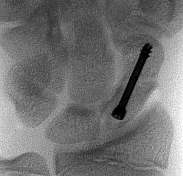

Question 21:

A 32-year-old female presents with a painless, slowly enlarging mass behind her knee. The radiograph is shown. Biopsy confirms a low-grade, bone-forming tumor on the surface of the posterior distal femur with a 'string sign' representing radiolucency between the tumor and the cortex. Which of the following genetic alterations is most classically associated with this diagnosis?

Correct Answer: MDM2 and CDK4 gene amplification

Explanation:

The clinical scenario and imaging description represent parosteal osteosarcoma, a low-grade surface osteosarcoma typically found on the posterior aspect of the distal femur. It is characterized molecularly by ring chromosomes and amplification of the 12q13-15 region, which includes the MDM2 and CDK4 genes. t(11;22) is associated with Ewing sarcoma. t(X;18) is seen in synovial sarcoma. GNAS mutations are found in fibrous dysplasia. EXT1 mutations are associated with hereditary multiple exostoses.